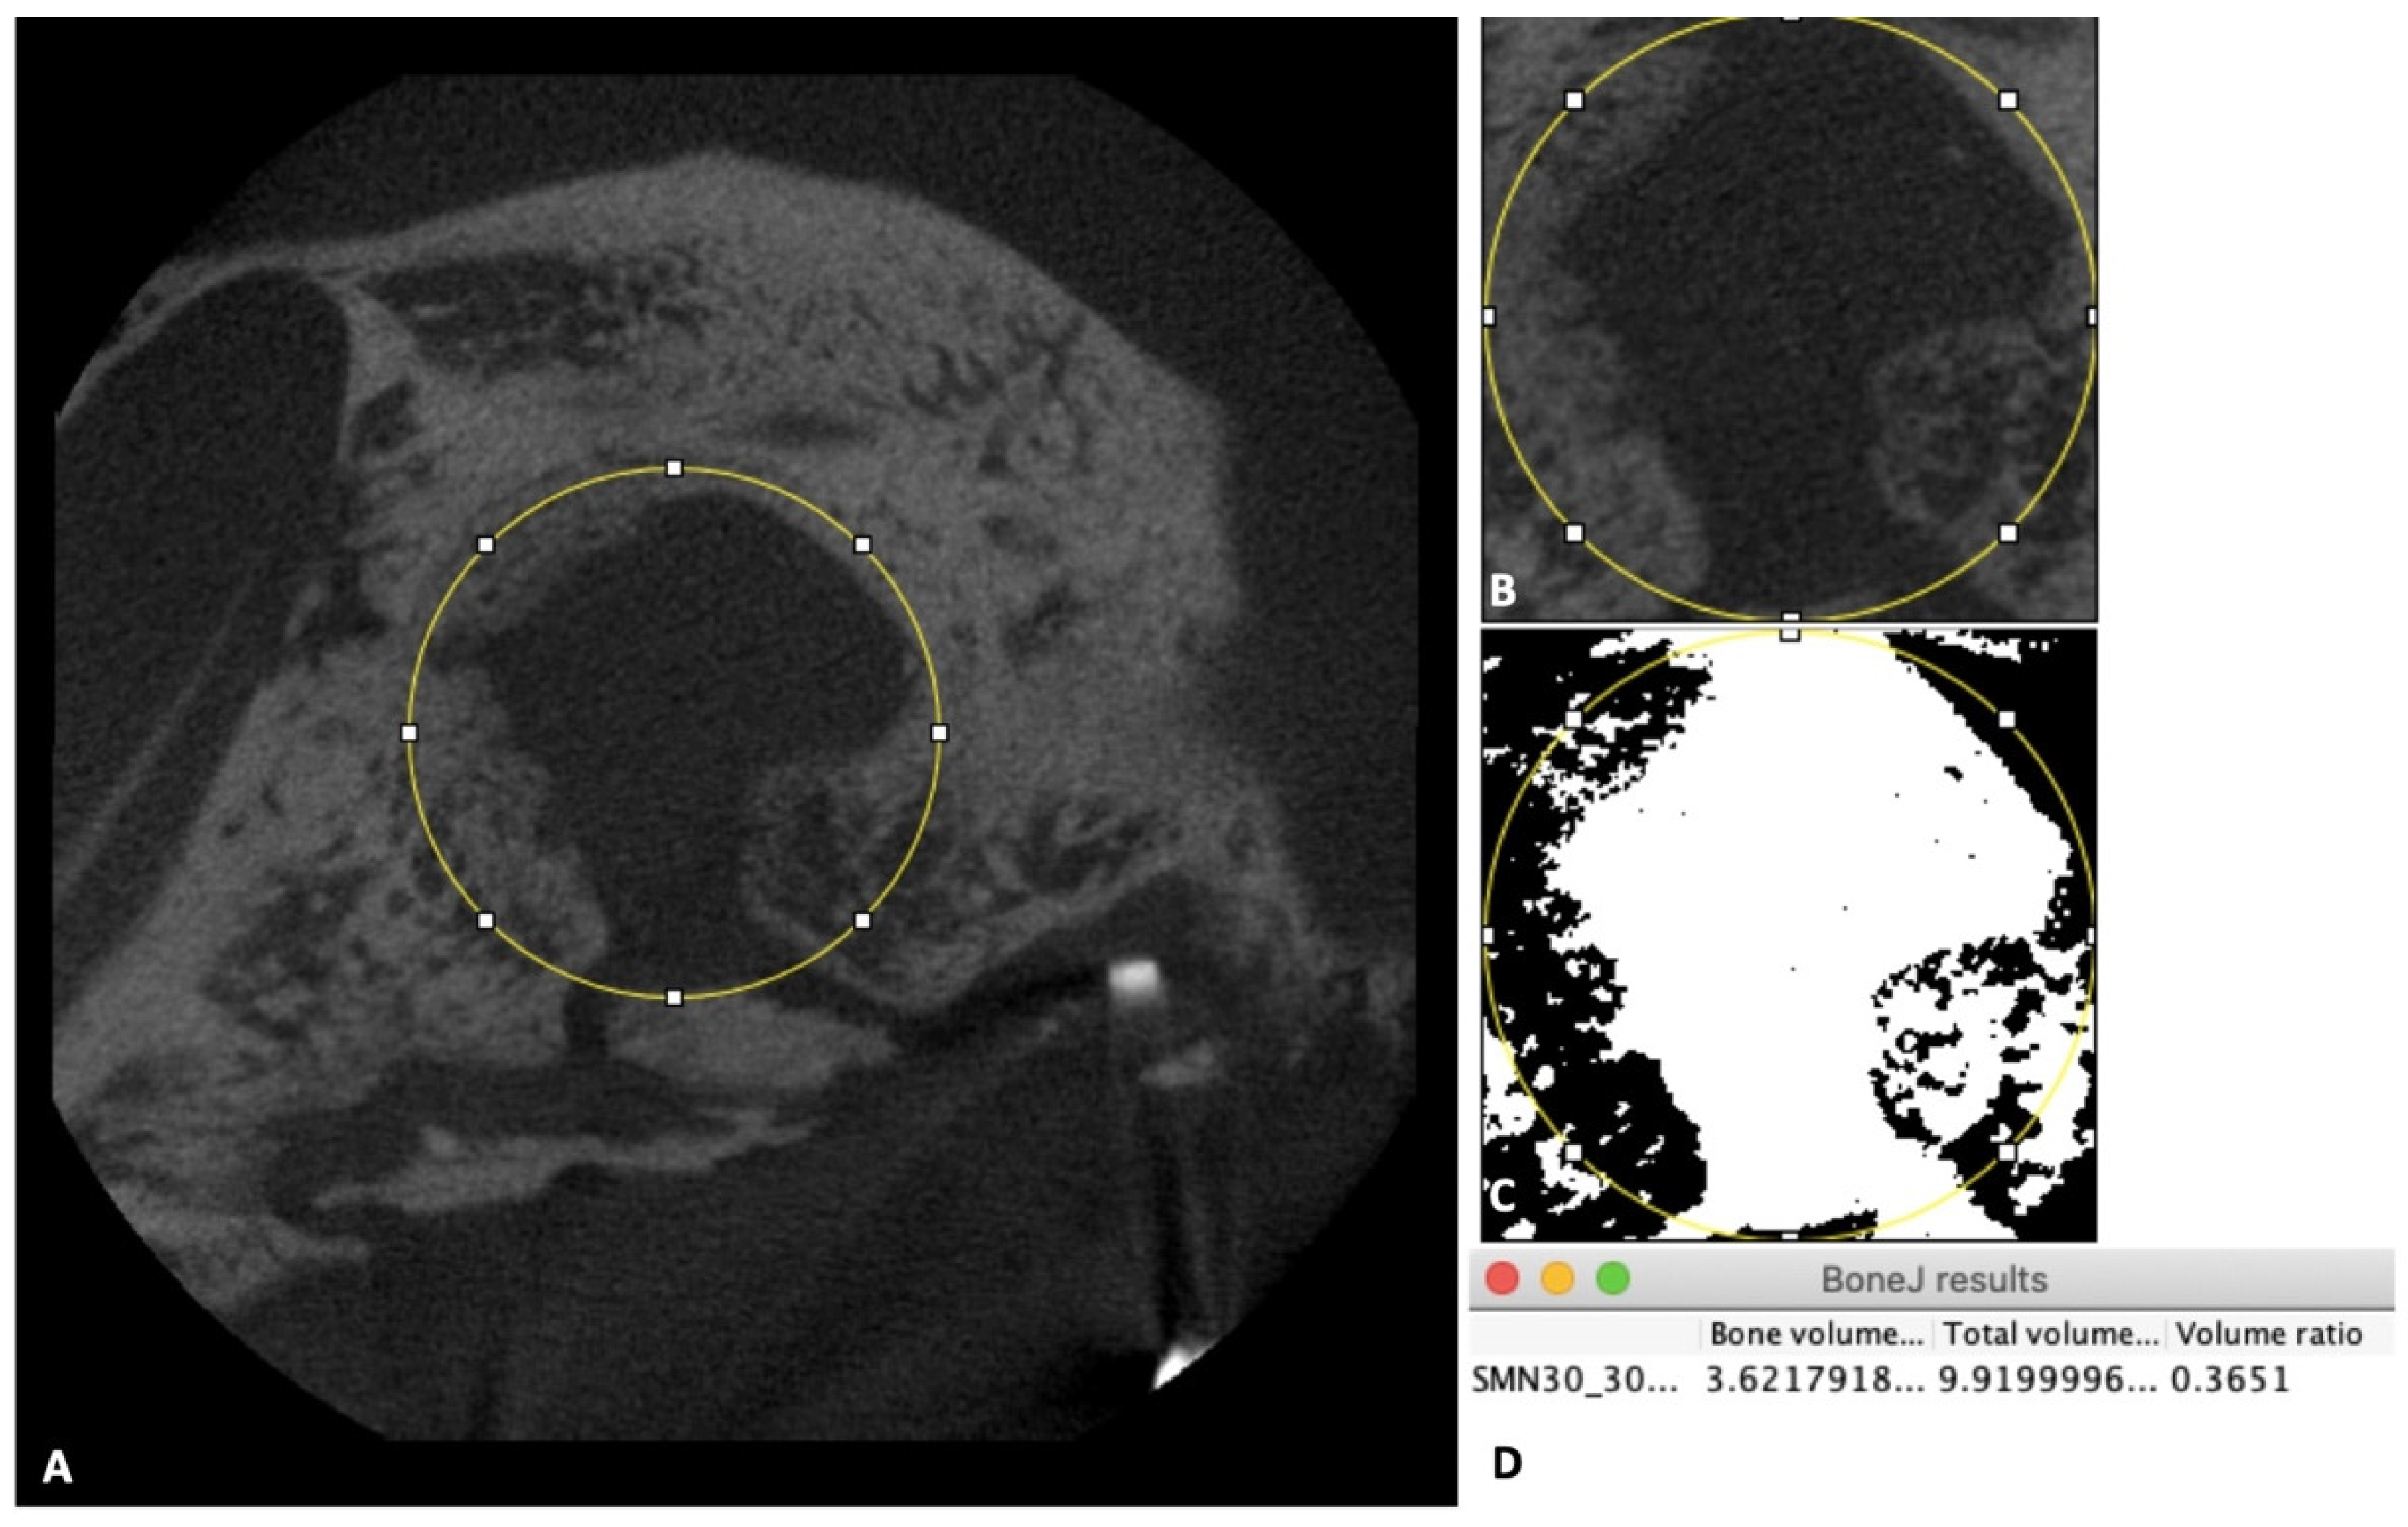

2.3. Micro-Computed Tomography (CT) Evaluation of the New Bone Formation

3.1. Micro-CT Evaluation